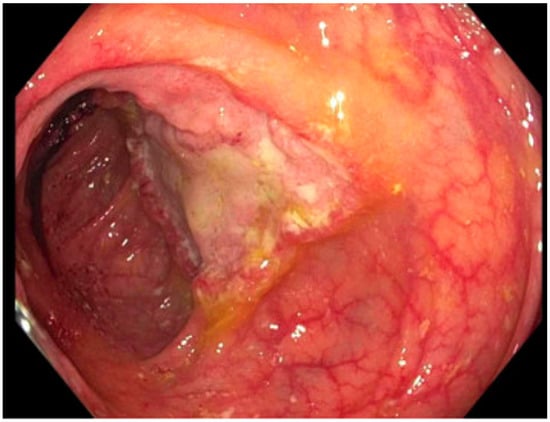

| 3: Histoplasmosis | 38 YO, 14 years post transplant. Symptoms of low-grade fever and weight loss prompted colonoscopy. |

CT chest/abdomen/pelvis: bowel wall thickening, lymphadenopathy, no acute pulmonary changes. Colonoscopy biopsy: Histoplasma (Figure 2). Histoplasma blood antibody: negative. Histoplasma urine antigen: 7.01 ng/mL. |